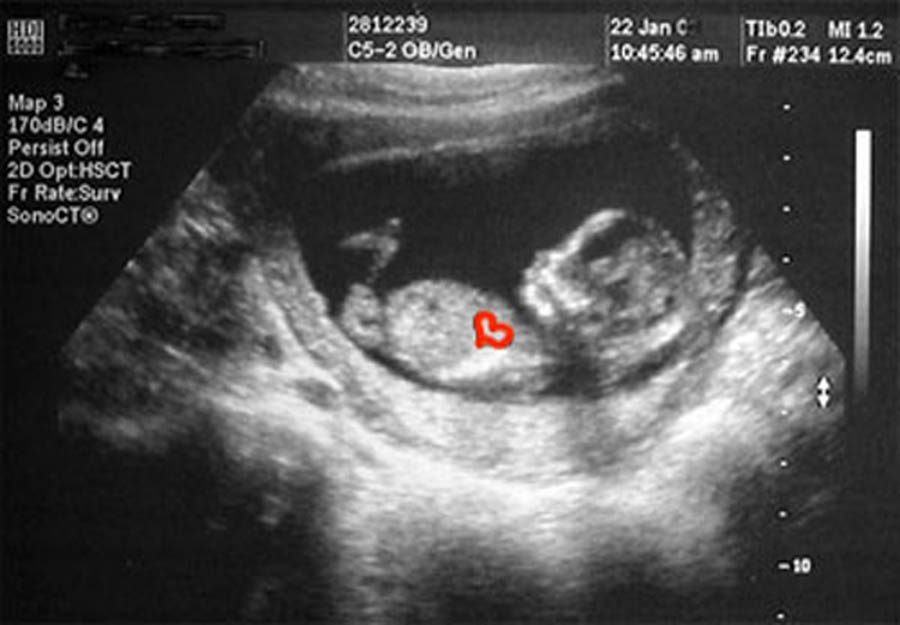

Gayle M. Irwin is an author and freelance writer residing in Casper, Wyoming. She served as Patient Resources Director for True Care Women’s Resource Center in Casper for nearly 13 years. She retired from the organization in December 2022 and now writes full-time. She’s published nearly 30 books, including the devotional, Seasons of Life, Seasons of Nature: Meditations on God’s Creation, published in 2025, that reflects upon how the various seasons of nature can correlate with the seasons people go through in life. Gayle is passionate about God’s creation and His creatures, and she advocates not only for pro-life causes for humans, but for the responsible stewardship of God’s creatures and His creation. Learn more about Gayle at her website: gaylemirwin.net.